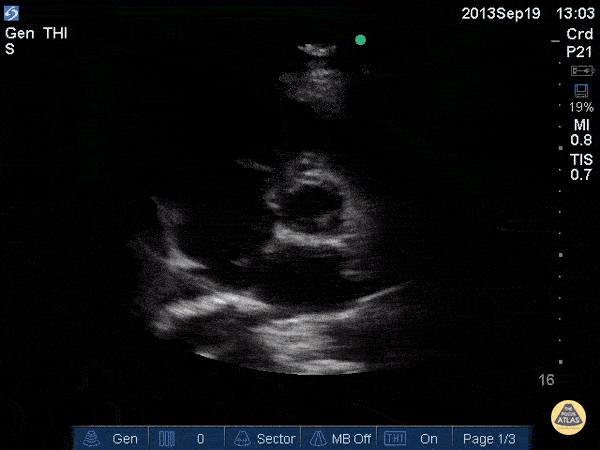

Recurrent fevers and this on PLAX:

Mitral valve Endocarditis